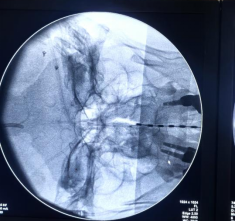

电极成功安置在高颈段

穿刺成功后固定电极